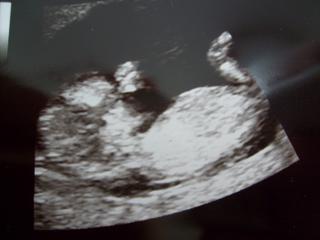

Ahojte dievčatá,tak ja mám po včerajšej poradni-spokojná nadmieru.Všetko je v najlepšom poriadku,bábatko spinkalo a rúčku malo položenú na očku-veď mrknite foto.Mam len nizky tlak-kavu slabu jednu denne podla odporucania lekara pijem,ale aj tak ma boli hlava-uz neviem,co mam robit-cim si zvysit tlak...vcera mi sestricka merala tlak,ked som mala jednu kavu v sebe a aj tak bol dost nizky ☹

Tu je aktualna foto nasho drobceka

@luci66 Dakujem,ty mas este krajsiu fotocku-skoda,ze moj doktor nema 3D ultrazvuk...nooo,ja netusim,kolko babatko meria,mne to sice doktor hovoril,ale v navale euforie,som si vsimala moje male kuriatko a jeho miery som prepocula 🙂 Viem len ze mi povedal,ze podla nich mi potvrdzuje termin porodu,lebo vsetko sedi 😉